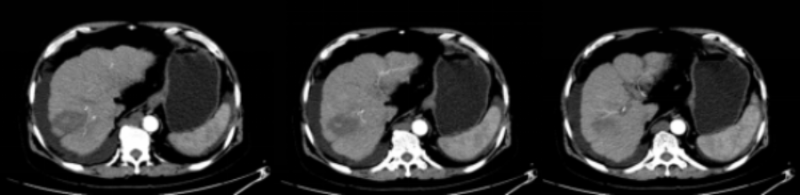

近日,68歲的楊大爺(化名)因“反復腹脹9年,再發(fā)1周”來我院就診。在醫(yī)生詳細詢問下,得知楊大爺既往有“乙肝、肝硬化”病史9年,收住感染科,入院后完善腹部增強CT顯示:考慮肝S8肝癌;肝硬化、脾大、腹水、門脈高壓,側(cè)支循環(huán)形成;腹腔多發(fā)增大淋巴結(jié);門靜脈主干及分支栓子。請腫瘤科會診,會診考慮到楊大爺肝腫瘤臨近橫膈,大小約2.2cm,肝硬化失代償期,Child-Pugh B級,手術(shù)風險大,綜合病情,醫(yī)生建議楊大爺行CT引導下經(jīng)皮微波消融治療肝腫瘤,在獲得了患者及其家屬的同意后,楊大爺轉(zhuǎn)入到腫瘤科進行微波消融術(shù)。

術(shù)前肝腫瘤情況,鄰近橫膈